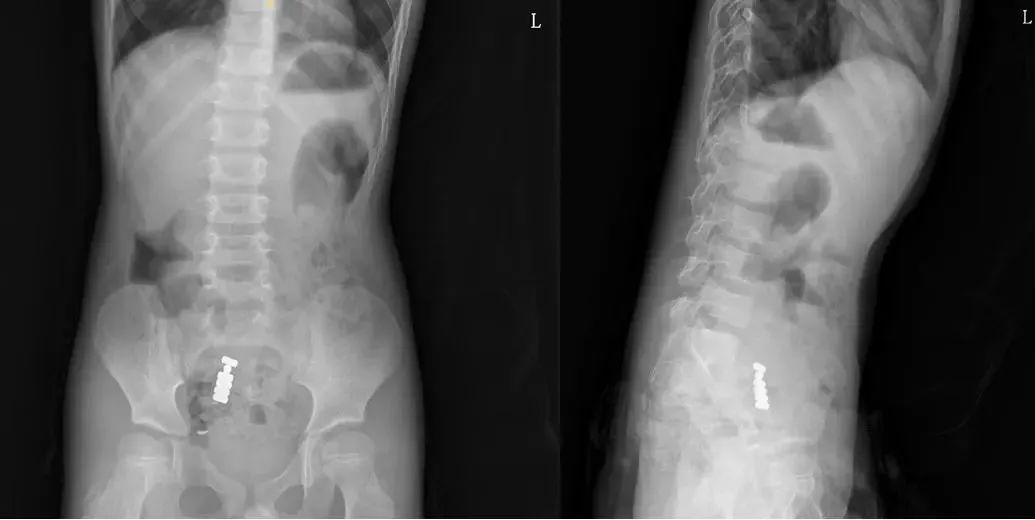

医生在他的胃部

意外发现一个黑色长方体异物

基于异物形态,医生初步判断可能是打火机。大爷这才回忆起自己三十多年前的轻狂往事,惊讶道:“这个打火机竟未排出啊!”

后来,医生团队通过胃镜将一只安全套送入胃腔,缓缓将整个打火机套入其中,最后通过异物钳将其缓慢拖拽出口腔,整个过程约20分钟。取出的打火机长约7厘米,外层覆盖黑色腐物。

令医生惊讶的是,尽管在胃内停留三十余年,打火机结构仍基本完整,机内居然还有残留液体。